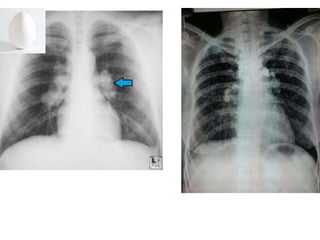

Chest X-ray of Uncomplicated

Silicosis

 Enlargement of hilar nodes may precede

parenchymal disease

 Uncomplicated silicosis has small round

opacities

 Egg-shell calcification of the hilum is

suggestive of silicosis

 Occasional can calcify

morphology

Chest X-ray ofUncomplicated Silicosis  Enlargement of hilar nodes may precede parenchymal disease  Uncomplicated silicosis has small round opacities  Egg-shell calcification of the hilum is suggestive of silicosis  Occasional can calcify